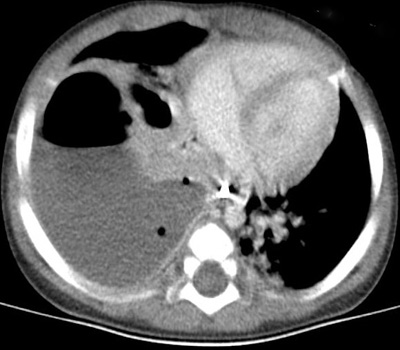

Example of an empyema. CT through the lower thorax shows a fluid collection in the right lower

pleural space with an air fluid level and a thick enhancing wall.